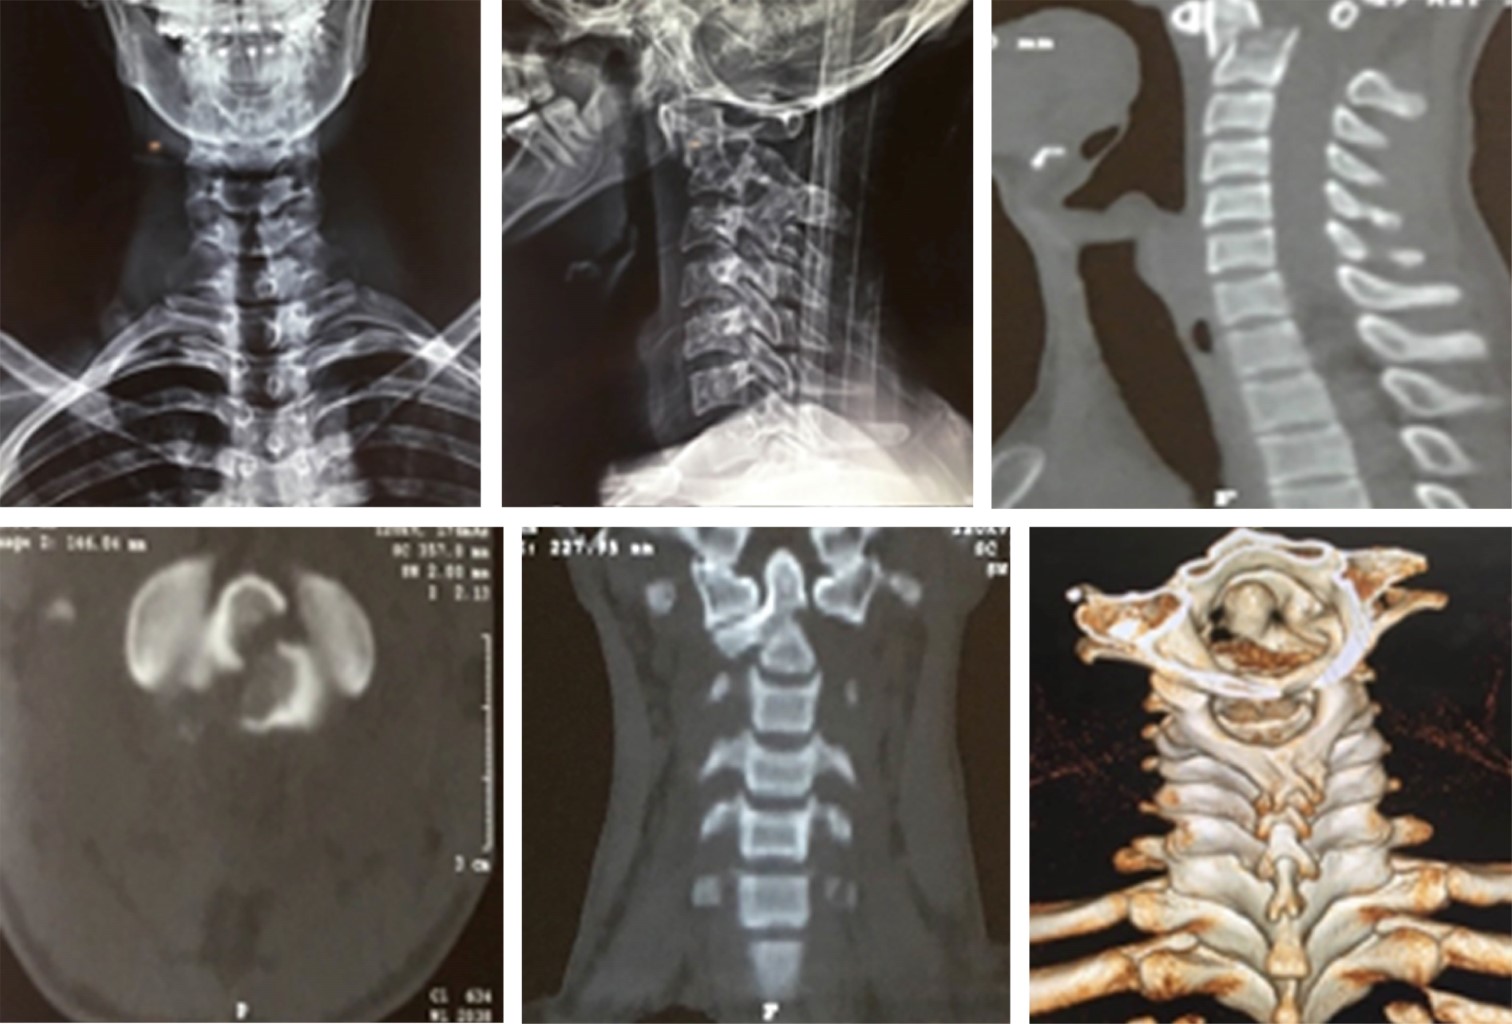

El tratamiento dependerá de la ubicación de la fractura de odontoides, según lo descrito por la clasificación de Anderson y D'Alonzo y los factores de riesgo del paciente para la falta de unión (la edad del paciente y sus comorbilidades) (Figuras 1 y 2).7 La osteosíntesis de las fracturas de la apófisis odontoides es un desafío debido a la anatomía y a las estructuras vecinas críticas que hacen que la fijación quirúrgica sea una tarea exigente.6,8

Figura 1

Figura 2